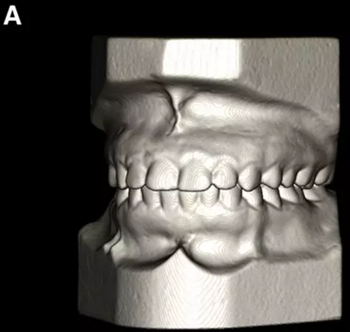

患者的上頜骨和下頜骨研究模型在最大牙尖交錯位時確定和數(shù)字化(圖2,A),作為咬合指導(dǎo)(咬合指導(dǎo))。該數(shù)字化咬合指導(dǎo)在齦緣周圍進(jìn)行數(shù)字化修剪,以便在CBCT掃描上可以更好得可視化(圖2,B)。

圖2. A,咬合時對象研究模型的右側(cè)舌側(cè)視圖掃描將作為未來指導(dǎo);該指導(dǎo)稍后用于將懸浮的下頜骨配對到修剪的上頜骨;B,左側(cè)舌側(cè)視圖的數(shù)字化修整牙合引導(dǎo)。